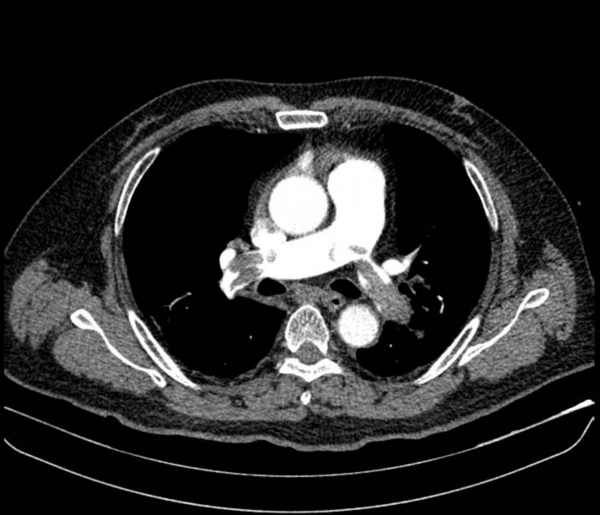

Hình ảnh chụp CT mạch máu phổi của bệnh nhân cho thấy huyết khối lớn bít tắc động mạch phổi hai bên

Kết quả điện tim và siêu âm tim cho thấy dấu hiệu quá tải thất phải cấp, điển hình của thuyên tắc phổi nặng. Ông L được dùng thuốc vận mạch ổn định huyết áp, sau đó chụp CT mạch máu phổi phát hiện huyết khối lớn bít tắc động mạch phổi hai bên.